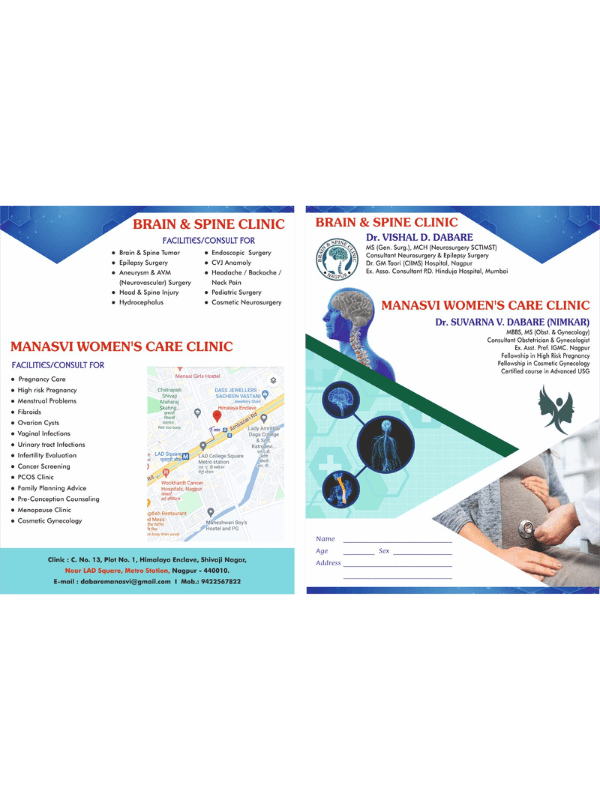

Dr. Vishal Dabare is a highly experienced neurosurgeon with over 1100 surgeries in brain and spine, including microscopic, endoscopic, and spinal instrumentation. He is skilled in both conservative and surgical management of neurological disorders, and he is committed to providing his patients with the best possible care. During consultations, Dr. Dabare focuses on understanding the patient's individual needs and goals. He then discusses all of the treatment options available, including the risks and benefits of each approach. He is also happy to refer patients to other specialists, such as radiation oncologists or medical oncologists, if necessary. If you are looking for a neurosurgeon who is skilled, experienced, and compassionate, then Dr. Vishal Dabare is the right doctor for you.

Dr. Suvarna Vishal Dabare Consultant Obstetrician and Gynecologist in Nagpur | Dr. Suvarna Vishal Dabare is a highly skilled and experienced Consultant Obstetrician and Gynecologist based in Nagpur, Maharashtra. With over 5 years of experience in the field, she is dedicated to providing comprehensive healthcare services to women, addressing a wide range of obstetric and gynecological concerns. Dr. Suvarna Dabare holds an MBBS degree and an MS in Obstetrics and Gynecology from Lokmanya Tilak Municipal Medical College and Sion Hospital in Nagpur. She has further honed her expertise through fellowships in High-Risk Obstetrics and Cosmetic Gynecology, as well as a certified course in advanced USG.

Dr. Vishal Dabare

Best Neurosurgeon in Nagpur | MBBS, MS GENERAL SURGERY- , MCH - NEUROSURGERY.

Dr. Suvarna Dabare

Gynaecologist & Obstetrician in Nagpur | MBBS, MS (OBGY), Fellowship in High Risk Obstetrics, Fellowship in Cosmetic gynecology, Certified course in advanced USGContact Us

Manasvi Clinic, Nagpur

C.N.13, Plot no 1, Himalaya Enclave, Shivaji Nagar, Near LAD Square Metro Station, Nagpur 440010

manasvidabare@gmail.com

+91 9422567822, 7045100195